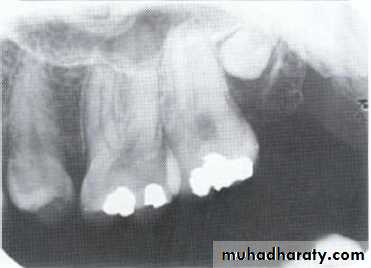

specimenX-Ray

Dilacerated root. The apical portion of the root is bent buccally or lingually into the plane of the central ray. Note the halo in the apical region, produced by the PDL

space (arrow).